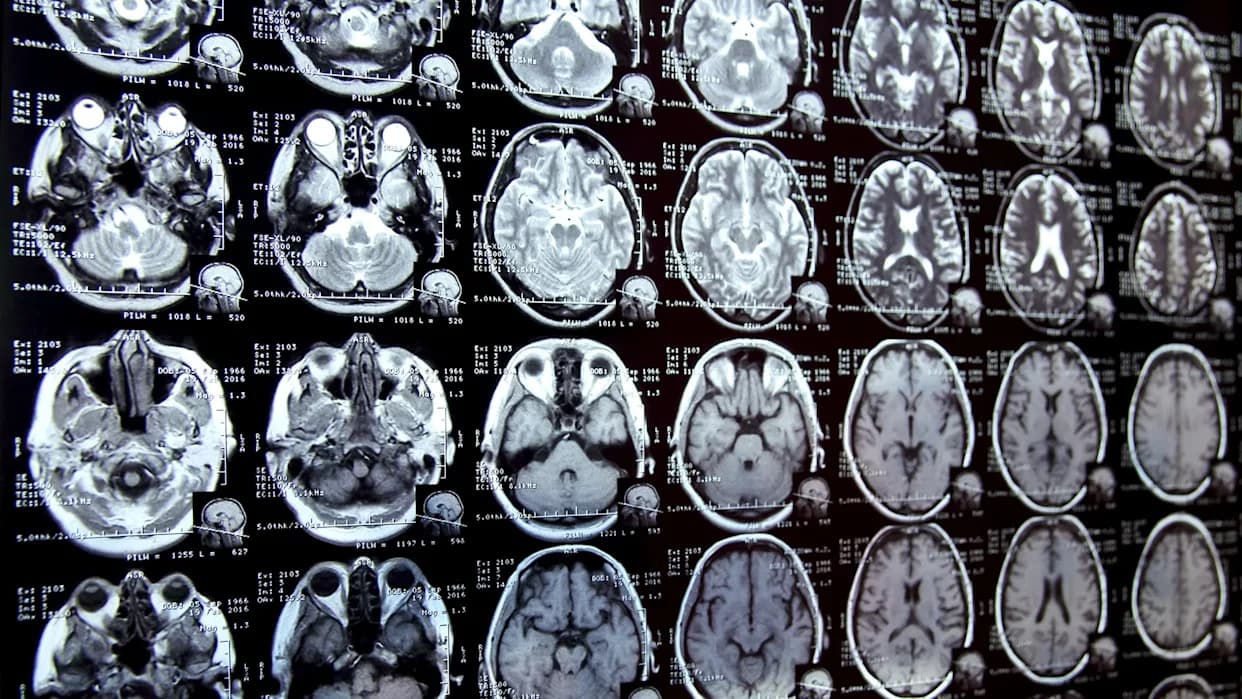

Plastično zagađenje više nije samo problem okeana — sve više dokaza pokazuje da mikroplastika ulazi i u ljudska tela, uključujući mozak. Nova studija izazvala je uznemirenje naučne javnosti nakon što su istraživači otkrili znatno veće količine mikroplastike u uzorcima moždanog tkiva prikupljenim 2024. u poređenju sa uzorcima starim osam godina.

Tim sa University of New Mexico utvrdio je da su uzorci iz 2024. godine sadržali skoro 50% više mikroplastike nego uzorci iz perioda pre osam godina. Prosečan mozak u toj analizi nosio je otprilike 7 grama plastike — otprilike jednakoj težini jednokratne plastične kašike ili, kako su mediji pribeležili, količini sličnoj pet čepova plastične boce.

Iako rezultati zabrinjavaju, naučnici naglašavaju da uzročno-posledične veze još nisu utvrđene. Istraživači su zabeležili više koncentracije mikroplastike u mozgovima osoba koje su imale demenciju, ali to može biti posledica promenjene propustljivosti krvno-moždane barijere kod tih osoba, što otežava uklanjanje stranih čestica i toksina.

Mikroplastika je već pronađena u placenti, krvotoku, pa čak i u prvom detetovom stolici, što ukazuje na široku i rastuću izloženost. Neke čestice su toliko sitne da mogu preći telesne barijere i dospeti u organe poput mozga. Rani radovi povezuju izloženost mikroplastici sa potencijalnim rizicima — od kognitivnog pada i hormona poremećaja do narušenog imuniteta i razvojnih problema kod dece — ali potrebna su detaljnija istraživanja da bi se ta rizika precizno kvantifikovala.